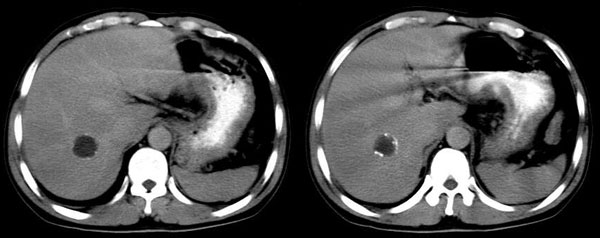

男,44岁,解黒便18天,胃镜:胃小角溃疡性质待查,表浅性胃炎。b超肝右叶占位。ct平扫肝右叶见一囊性占位,ct值:18hu,壁呈带状高密度钙化,增强扫描未见强化。考虑:囊肿?但壁钙化第一次见,不能确定,病人是南方石山地区,未到过牧区,能否排除包虫?

增强扫描:病灶未强化。

肝囊肿,班囊壁钙化。肝脓肿壁要厚的多,即使治疗后内部密度应该不均,可有分隔。

右肝后叶内圆形囊状影,包膜完整,断续钙化.

意见:右肝囊肿并钙化